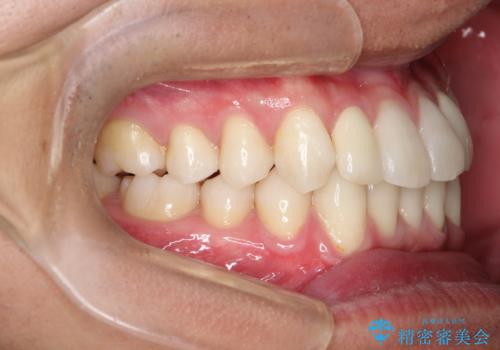

- 前歯のがたつきが気になるとのことで来院されました。

骨格的なところと、上下の歯の大きさのことを考慮して、下の前歯を1本抜歯し、インビザラインにて矯正治療することとなりました。

上の前から2番目の歯がもともと小さかったため、最後にかぶせ物を装着することで、自然な仕上がりにできました。